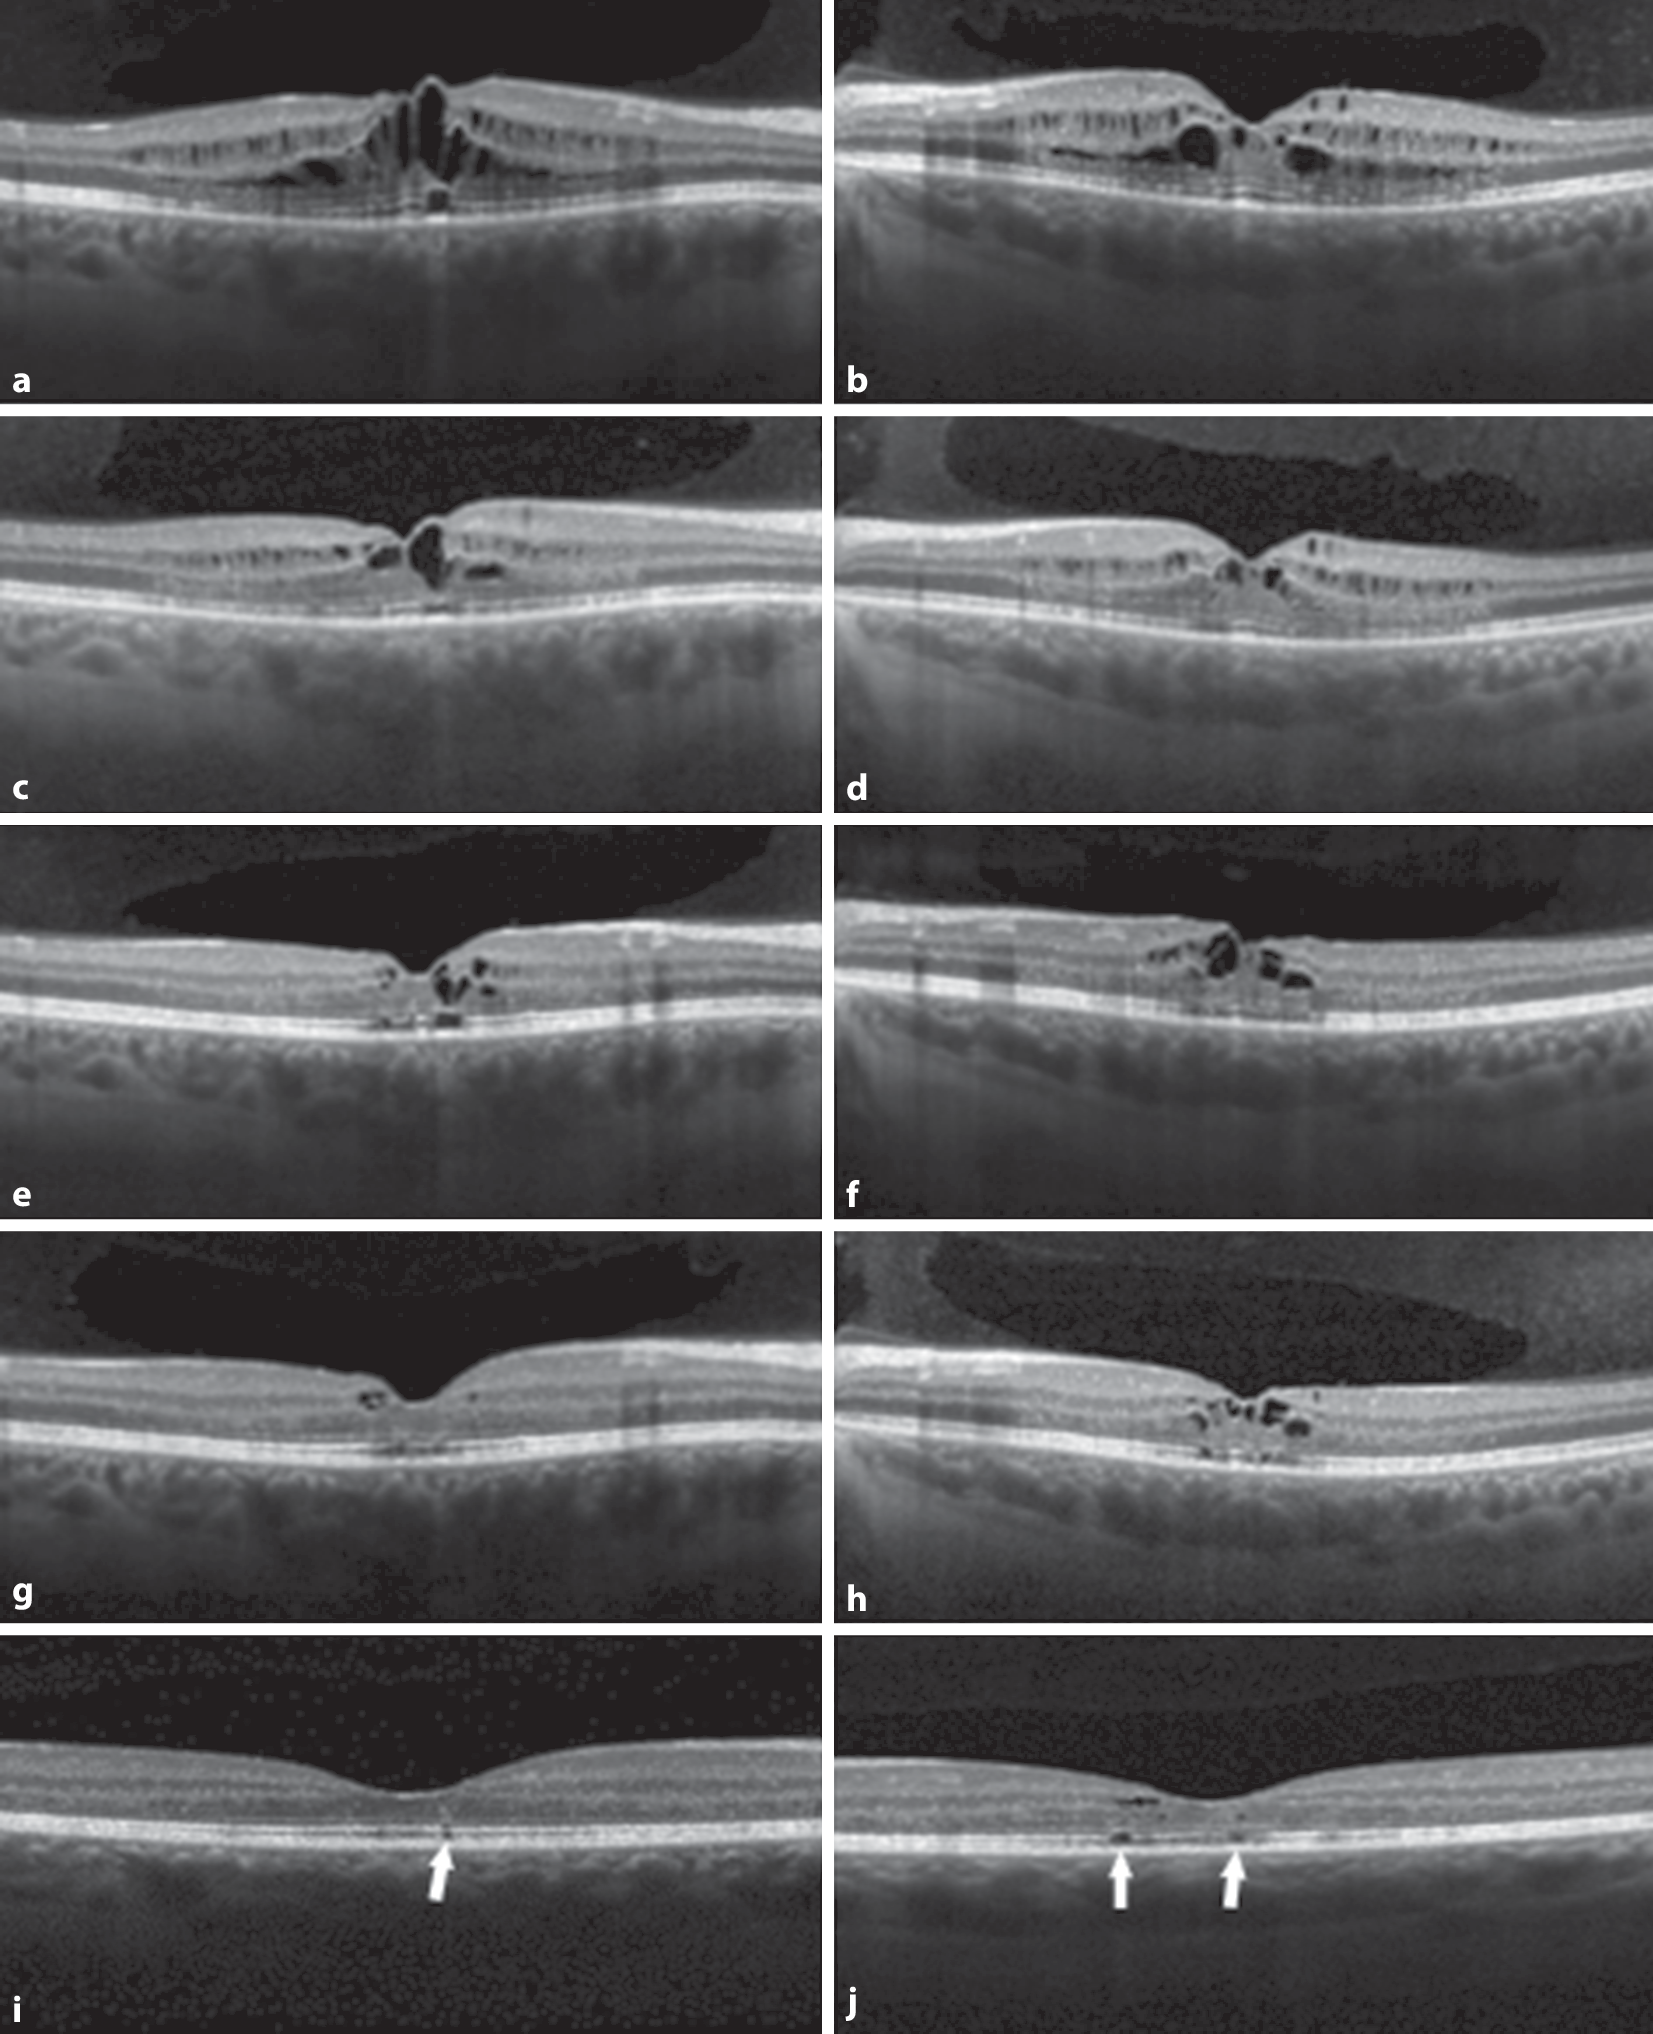

Abb. 2

SD-OCT beider Augen im zeitlichen Verlauf über 13 Monate: 2 Wochen (ab), 7 Wochen (cd), 6 Monate (ef), 11 Monate (gh) und 13 Monate (ij) nach Erstbefund. Neben einer Regression des Makulaödems zeigen sich Läsionen innerhalb der ellipsoiden Bande (Pfeile)

Nach Absetzen der Niacin-Einnahme kann eine Befundbesserung innerhalb von Tagen bis mehreren Monaten eintreten [6, 8, 10]. In unserem Fall zeigte sich erst im Verlauf von 13 Monaten eine Befundbesserung mit persistierenden fokalen Unterbrechungen in der ellipsoiden Bande (Abb. 2e).